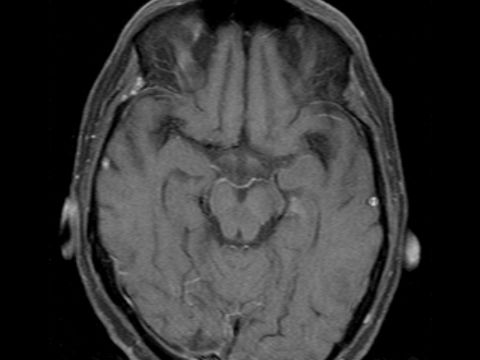

43 yaşında erkek hasta son 1 yıldır akciğer kanseri (Skuamöz hücreli kanser) tanısı ile takip edilirken beyinde 1 adet metastaz tespit edildi.

Tüm beyin ışınlaması sonrası sağ oksipital metastatik tümörün küçüldüğü ancak kaybolmadığı izlendi.

Tarafımızca hastaya Gamma-Knife tedavisi uygulandı.

Gamma-Knife tedavisi sonrası tümörün tamamen kaybolduğu izlendi.